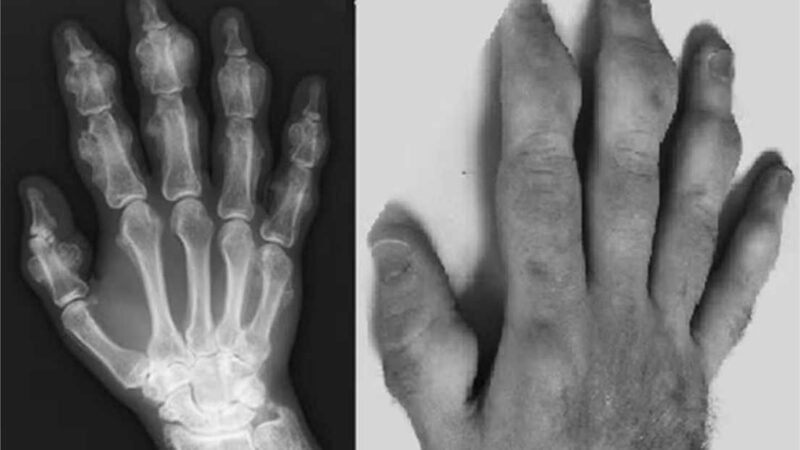

Em 2010, um morador da região de Nova Inglaterra, nos Estados Unidos, surpreendeu a comunidade médica local